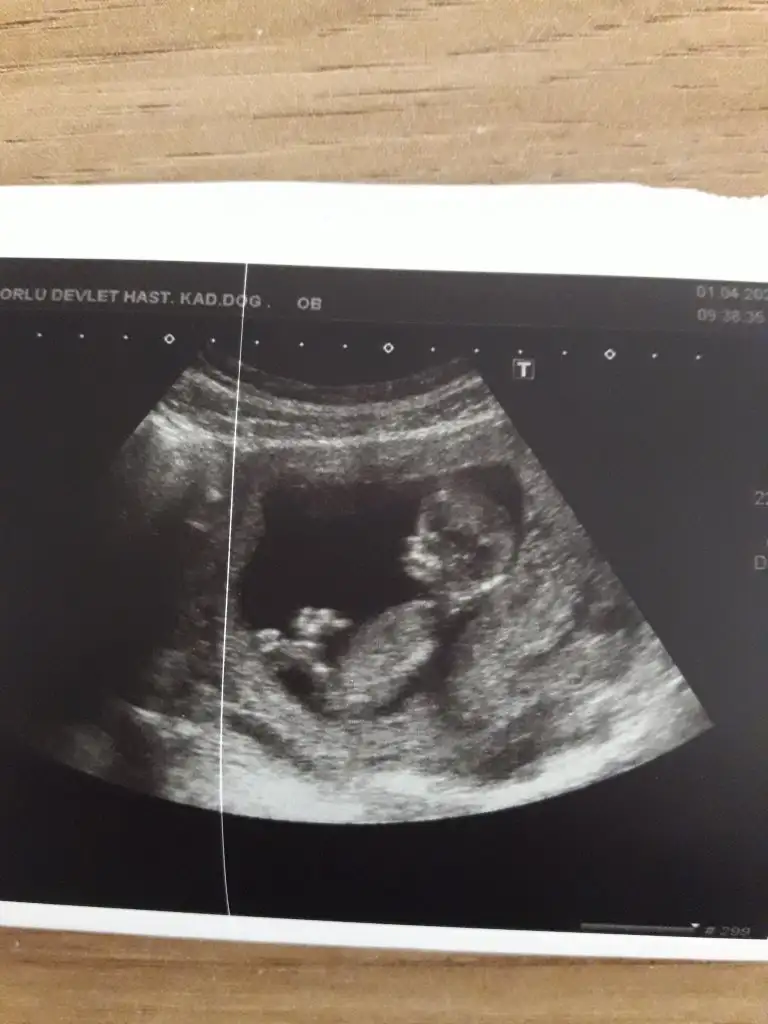

prenses uzanmış12+1 karından ultrason. Doktor bi kıza benziyor dedi bi erkeğe sizde tahminde bulunur musunuz

Yaaa belli diyorsunuz bakalımprenses uzanmış

kuzum Prenses gibi duruyor